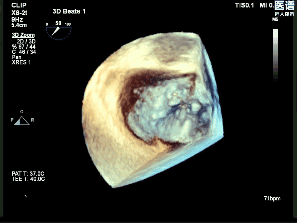

超声心动图(经胸超声心动图,TTE)示:

左心室射血分数(LVEF):75%,左心房前后径:38mm;

二尖瓣P2区大部分瓣叶在收缩期脱入左心房,断裂腱索残端摆动,呈连枷样运动;

连枷宽度:15mm,连枷间隙:6mm;

二尖瓣环AP径:33mm;

AL-PM径:35mm;

有效反流口面积(EROA):0.67cm²。

超声心动图诊断:

二尖瓣反流(退行性,CarpentierⅡ型,4+);

二尖瓣后叶脱垂伴腱索断裂。

术前超声影像

3D

3D彩

术前超声